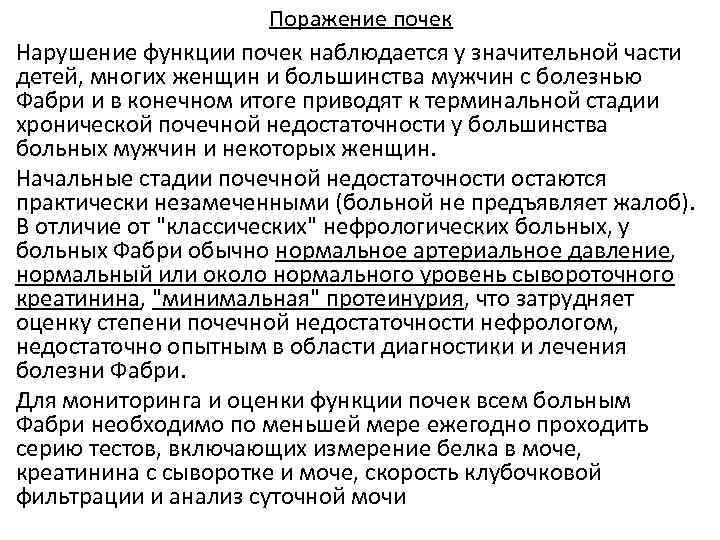

Поражение почек Нарушение функции почек наблюдается у значительной части детей, многих женщин и большинства мужчин с болезнью Фабри и в конечном итоге приводят к терминальной стадии хронической почечной недостаточности у большинства больных мужчин и некоторых женщин. Начальные стадии почечной недостаточности остаются практически незамеченными (больной не предъявляет жалоб). В отличие от "классических" нефрологических больных, у больных Фабри обычно нормальное артериальное давление, нормальный или около нормального уровень сывороточного креатинина, "минимальная" протеинурия, что затрудняет оценку степени почечной недостаточности нефрологом, недостаточно опытным в области диагностики и лечения болезни Фабри. Для мониторинга и оценки функции почек всем больным Фабри необходимо по меньшей мере ежегодно проходить серию тестов, включающих измерение белка в моче, креатинина с сыворотке и моче, скорость клубочковой фильтрации и анализ суточной мочи